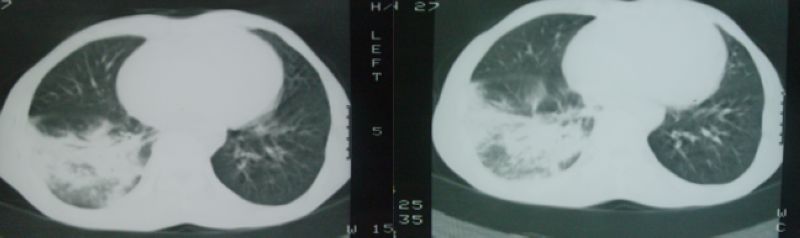

以下是引用hyhxn在2008-4-16 18:10:00的发言:[br]右中下肺炎症感染,没有纵隔窗?